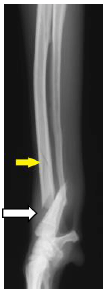

1. ボルゾイの前足の骨折(橈尺骨骨折)

ボルゾイという大型犬の前足を横から見たレントゲン写真です。 前足の骨が折れて曲がっています。(白矢印) 骨にヒビが入っている部分もあります。(黄色矢印) |